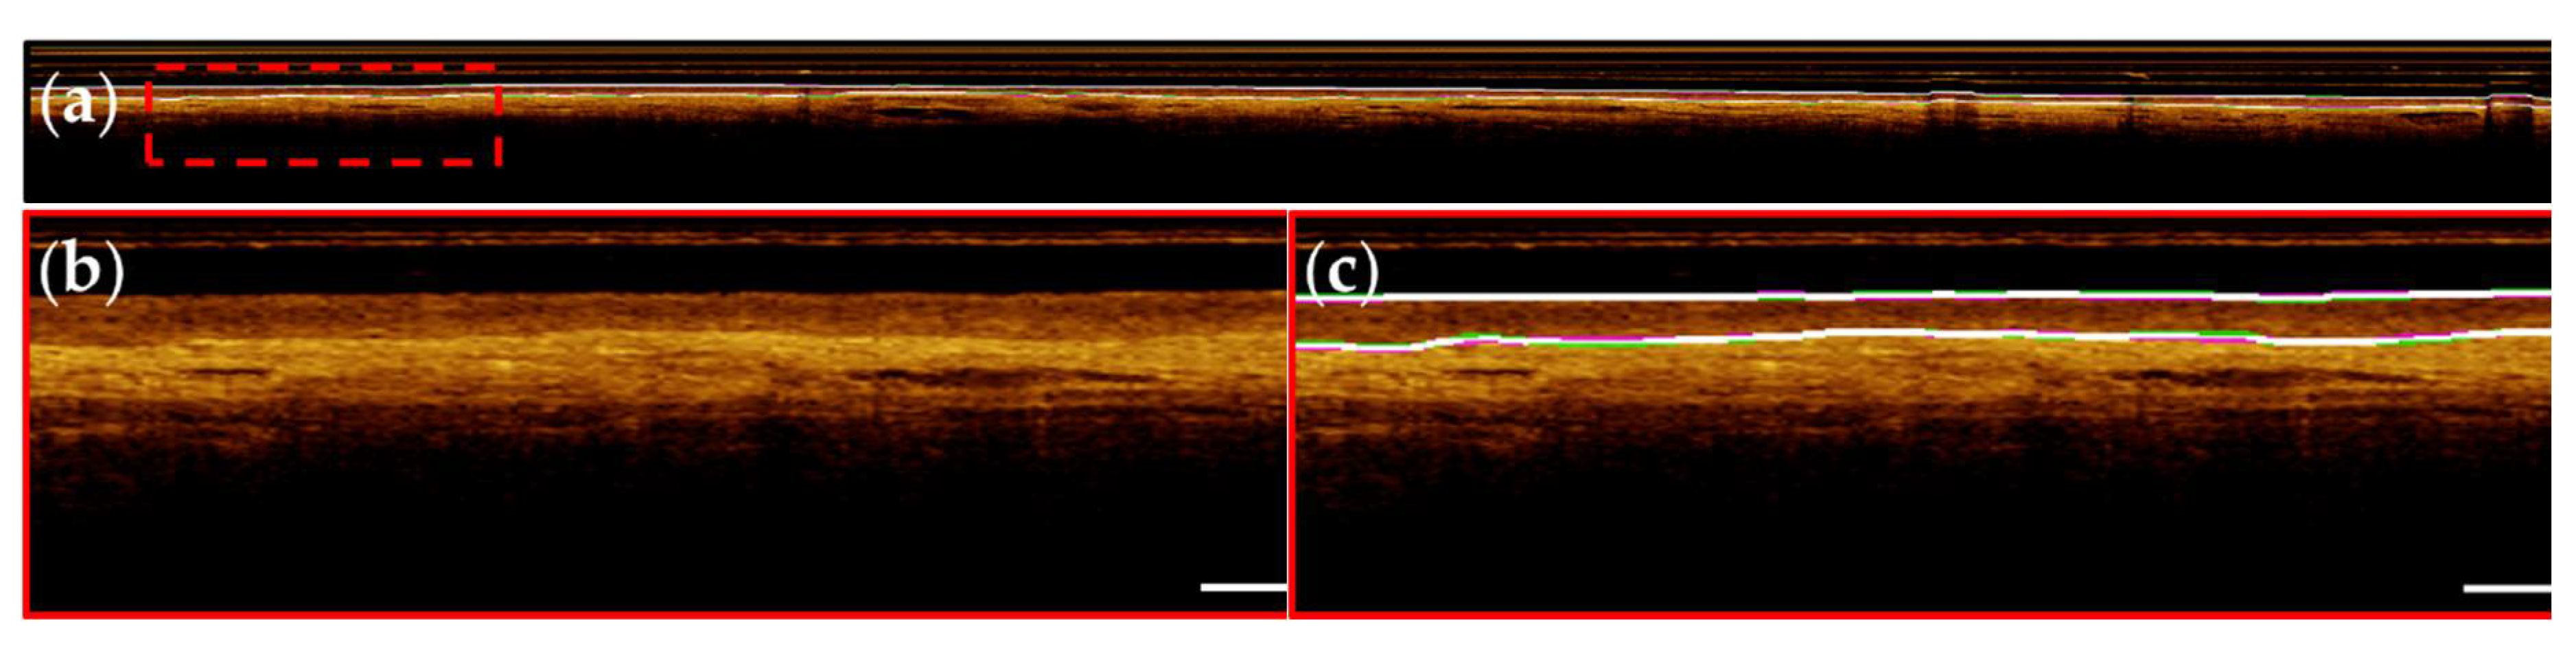

- Surface segmentation. A shallow u-net was used to segment the (epithelial) tissue surface.

- Basement membrane segmentation. A shallow u-net was used to segment the basement membrane.